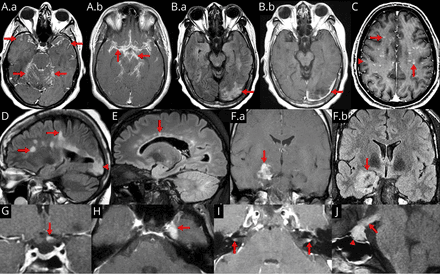

Right image: MRI brain with contrast showing near resolution of enhancement after treatment.

The diagnosis of neurosarcoidosis often is difficult. Definitive diagnosis can only be made by biopsy (surgically removing a tissue sample). Because of the risks associated with brain biopsies, they are avoided as much as possible. Other investigations that may be performed in any of the symptoms mentioned above are computed tomography (CT) or magnetic resonance imaging (MRI) of the brain, lumbar puncture, electroencephalography (EEG) and evoked potential (EP) studies. If the diagnosis of sarcoidosis is suspected, typical X-ray or CT appearances of the chest may make the diagnosis more likely; elevations in angiotensin-converting enzyme and calcium in the blood, too, make sarcoidosis more likely. In the past, the Kveim test was used to diagnose sarcoidosis. This now obsolete test had a high (85 percent) sensitivity, but required spleen tissue of a known sarcoidosis patient, some of which was injected into the skin of a suspected case.[1]

MRI with gadolinium enhancement is the most useful neuroimaging test. This may show enhancement of the pia mater or white matter lesions that may resemble the lesions seen in multiple sclerosis.[1]